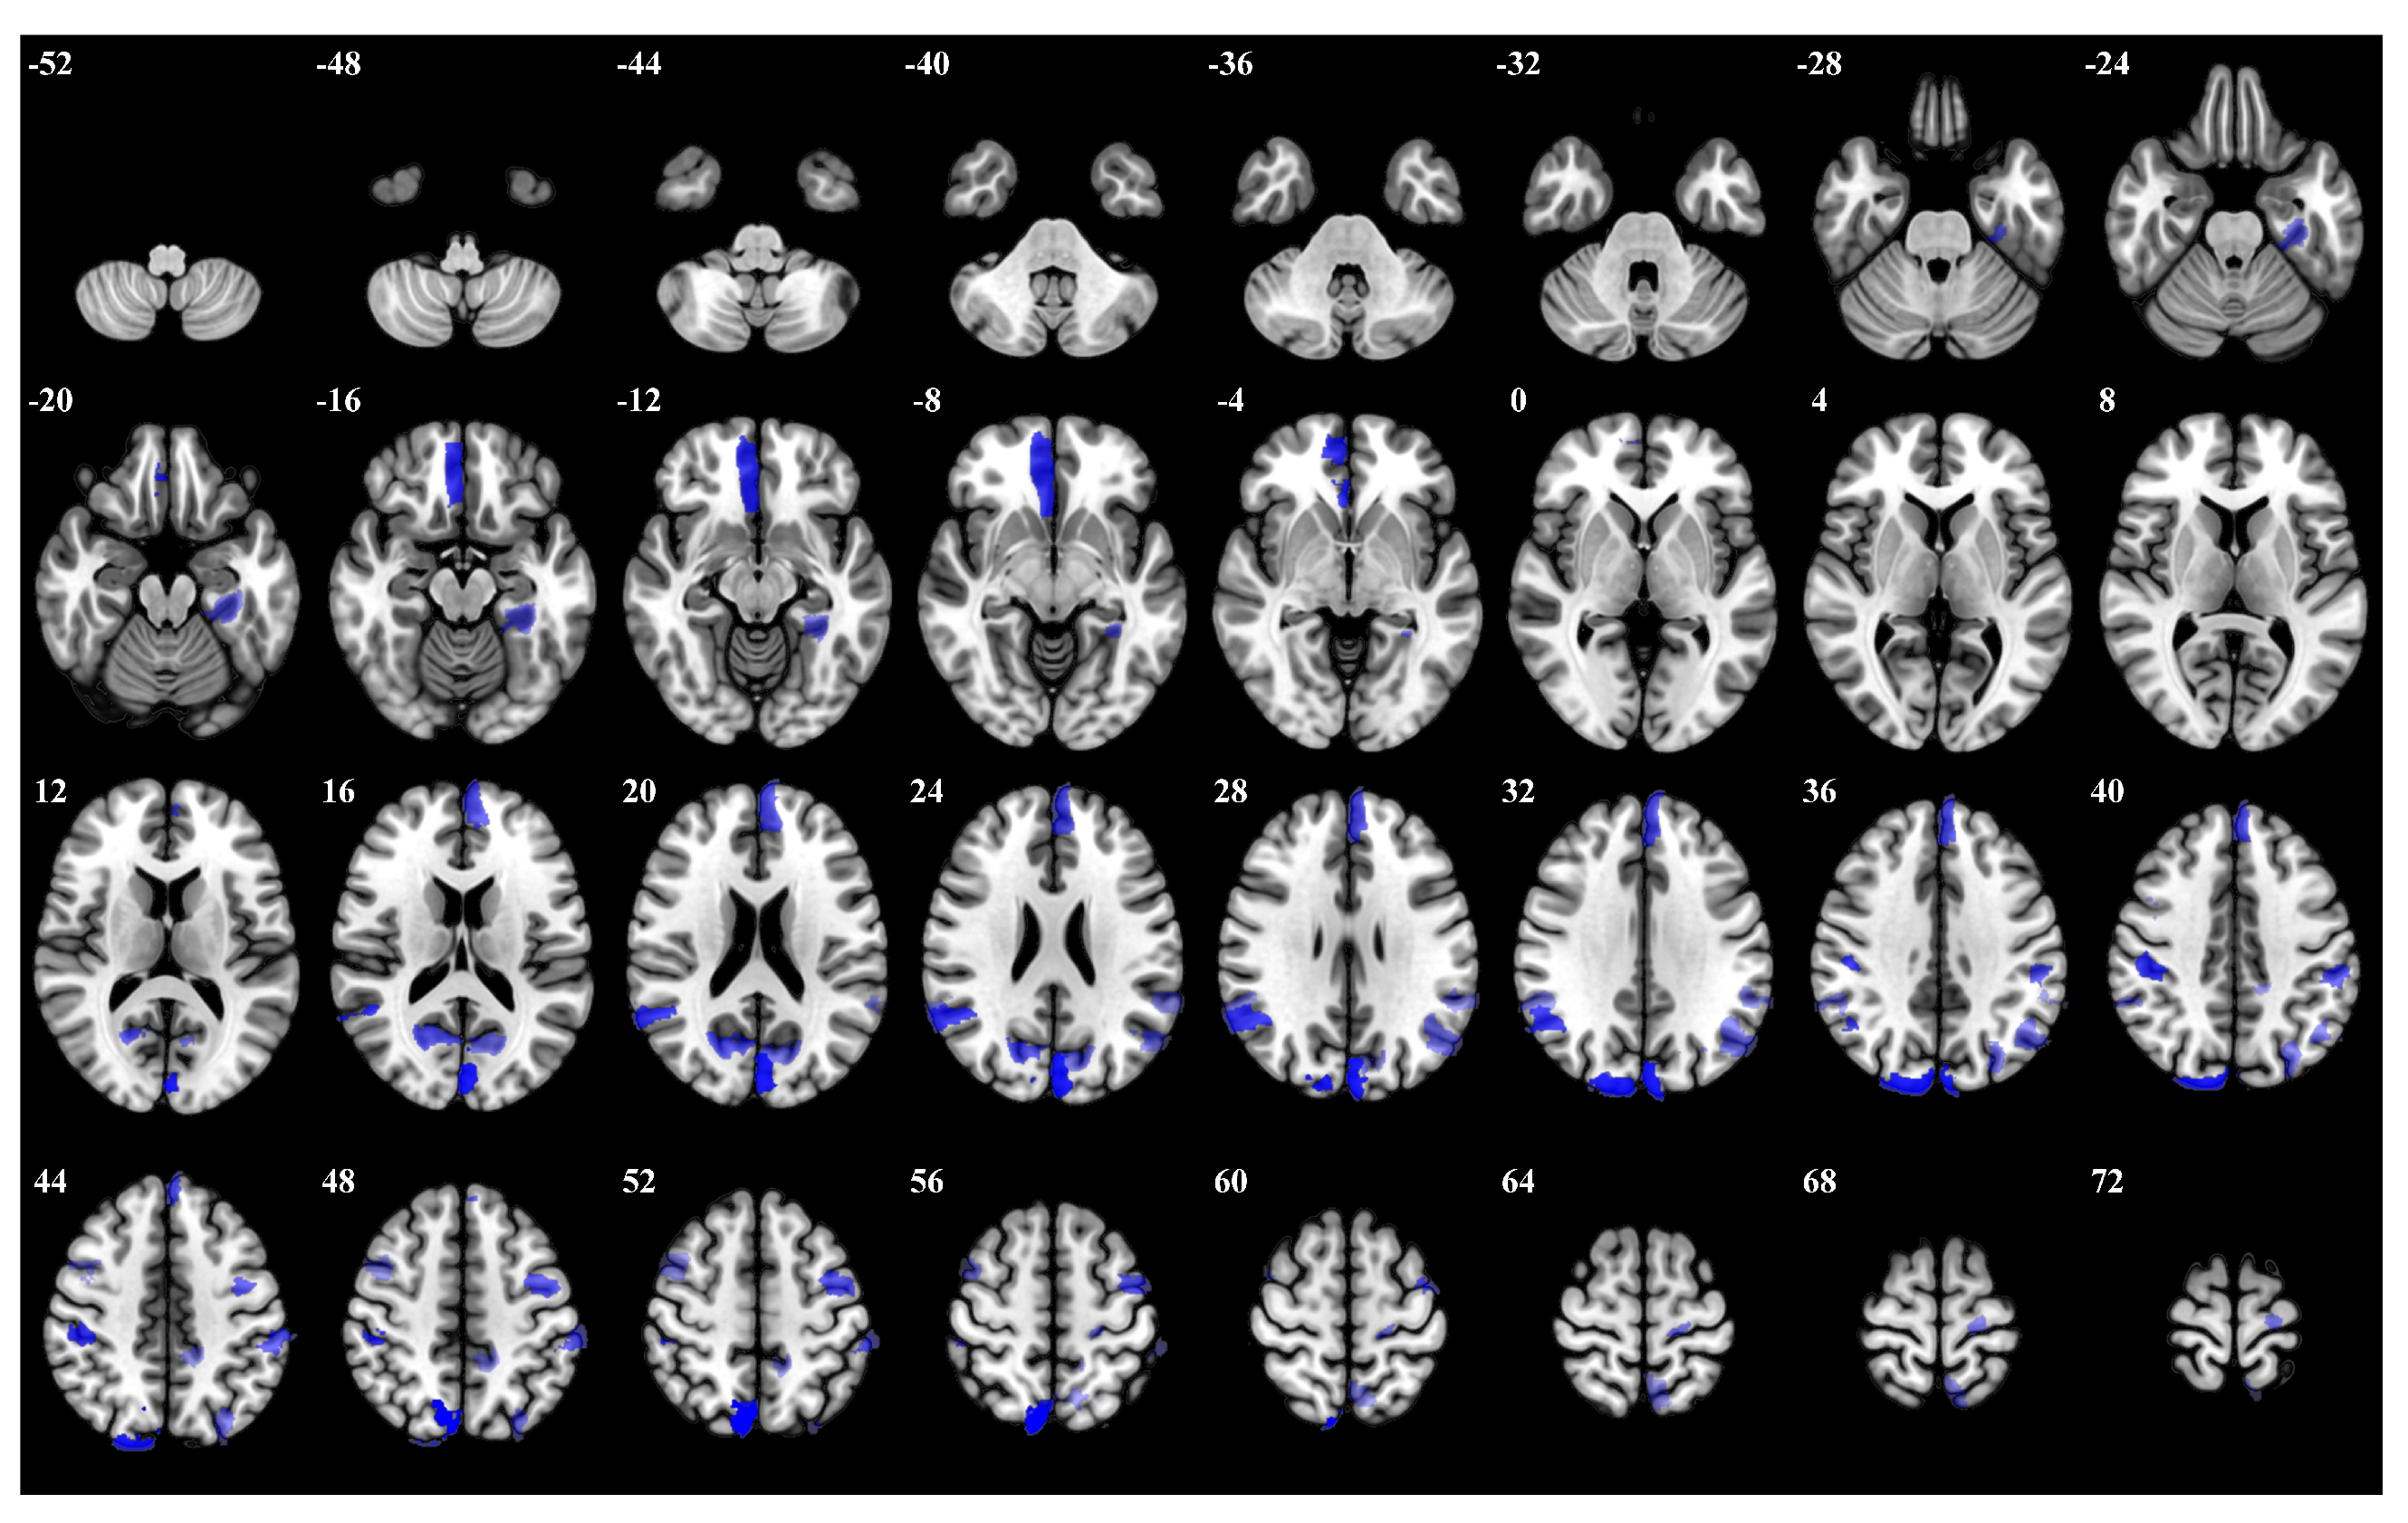

| Rank | Brain Regions | Side | Centroid Coordinates (R A S) | Importance Weight |

|---|---|---|---|---|

| 1 | Dorsal Attention Posterior 15 | R | 8 −71 53 | 0.287 |

| 2 | Visual 25 | L | −3 −84 24 | 0.285 |

| 3 | Visual 29 | R | 16 −87 36 | 0.256 |

| 4 | Visual 19 | L | 5 41 −11 | 0.255 |

| 5 | Dorsal Attention Posterior 9 | R | 45 −28 42 | 0.252 |

| 6 | Default Parietal 3 | R | 53 −53 26 | 0.241 |

| 7 | Visual 24 | R | 16 −66 19 | 0.237 |

| 8 | Dorsal Attention Frontal Eye Fields 1 | L | −40 −3 51 | 0.227 |

| 9 | Default Prefrontal Cortex 13 | L | −4 51 28 | 0.223 |

| 10 | Dorsal Attention Posterior 6 | L | −55 −32 45 | 0.218 |

| 11 | Frontoparietal Control Parietal 1 | L | −29 −74 42 | 0.214 |

| 12 | Visual 2 | L | −30 −33 −18 | 0.203 |

| 13 | Default Parietal 4 | L | −47 −64 31 | 0.200 |

| 14 | Visual 26 | L | −12 −71 20 | 0.195 |

| 15 | Somatomotor 31 | L | −19 −24 67 | 0.185 |

| 16 | Salience Ventromedial Attention Parietal Operculum 2 | L | −58 −44 27 | 0.183 |

| 17 | Default Parietal 4 | R | 55 −45 33 | 0.182 |

| 18 | Salience Ventromedial Attention Medial 5 | L | −13 −41 47 | 0.180 |

| 19 | Dorsal Attention Posterior 15 | L | −7 −59 63 | 0.177 |

| 20 | Frontoparietal Control Lateral Prefrontal Cortex 13 | R | 43 7 51 | 0.176 |